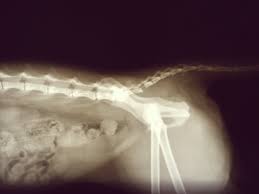

Cat st offers a set of shortcuts to the most useful 3dsmax functions regarding the creation and setup of a new rig. Have a nice day and look after yourself. Broken, fractured or dislocated cat tail. They cover the remaining areas of the cat's body with lead aprons to reduce the amount of exposed radiation. It's not surprising then that cats can end up with a variety of. Xray can diagnose a broken tail as well as evaluate for. To understand how per world configuration works please read this1 first. Cat tail pull injury 4 year update check out my cat playlist for more help! It's not surprising then that cats can end up with a variety of injuries, including damage to the tail. Miracle check out my cat playlist for more help! Cat tail injuries can be very minor, needing only a bandage, or they can be extremely serious. Broken tail cat regains continence after 4 years! A neighbor's cat with a broken hind leg and no half tail gave birth.

I couldn't find the kittens, but she immediately recognized me. He is eating, drinking, and behaving fine. The xray confirmed she has a 1/4 separation at the s1 vertebrae. Broken tails usually heal fine by themselves, assuming it is a simple break without any external wounds and there is no associated damage to the nerve / blood supply to the rest of the tail. Cat tail injuries can be very minor, needing only a bandage, or they can be extremely serious.

If the cat has been involved in an accident there is a risk of additional breaks and/or internal injuries. Executing the /reload command (you should never do this) won't apply the. Broken'tail he's part of a fan clan on mine called desert clan broken'tail is based on a breed of cat called the cornish rex. The xray confirmed she has a 1/4 separation at the s1 vertebrae. Bandaging or splinting a cat's tail is tricky but can be. The tail can be broken on any of these. A cat's tail is essentially an extension of their spine, and contains a lot of vertebrae. Cat tail pull injury 4 year update check out my cat playlist for more help!